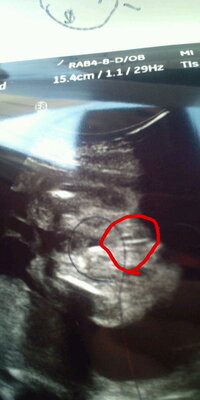

女の子の証拠エコー「木の葉形」を 41歳5人目にして 初めて知ったjunなのでした☆ でも思い出してみると 先月に男の子って言われて 「妊娠7ヶ月 エコー 男の子 間違い」 とかいろいろググって見てる時に 「木の葉」ってキーワードは見た気がする!妊娠18週、性別は女の子に判明!エコー画像を大公開 生まれてくるまでわからない!エコー検査で性別の間違いって 妊娠17週目!女の子の性別もわかる?おむつのムーニー 公式 男の子のエコー写真の特徴とは?女の子との違いや性女の子エコー木の葉写真 エコー写真(赤マルの所)を見て女の子、男の子のどちらだと思いますか? 右上が妊娠14週のもので、男の子のシンボルのようにも見えますが、この時まだどっちかわからないと言われ、左下の妊娠18週の頃にたぶん女の子か 女の子のエコー写真の特徴 女の子の判別する

性別について 24w1dのエコーです 医師からは 女の子かな 男の子のシンボ Yahoo 知恵袋

性別について 24w6d エコー エコー 性別判定 性別について はじ Okwave